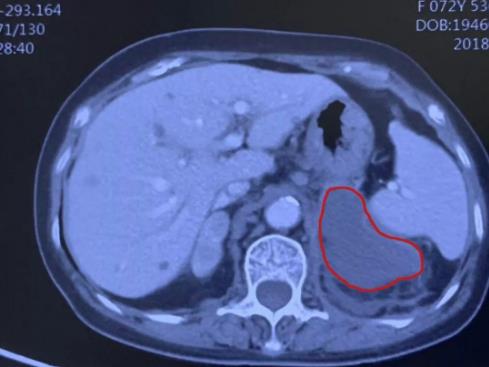

兩個月后,李阿婆回到廣州復大腫瘤醫院進行復診。根據以往經驗,醫生們原本打算對她的病情進行第二次消融的,但經過影像學檢查,發現剩余的腫瘤基本已經完全壞死了!也就是講原本只消融了90%的腫瘤,現在連剩余的腫瘤也死亡了,老人家完全不需要做第二次消融了!這個意外的驚喜令李阿婆與家人感到特別地開心,李阿婆家人評價說:“真沒有想到廣州復大醫院竟然會有這樣的技術!”

據牛立志教授介紹,為什么這位老人家只消融了90%的腫瘤,而影像學上過后看完全消失了呢?這是因為,進行冷凍消融后,腫瘤大部分壞死之后,它可以引起“旁觀者效應”。就像是把一個壞人消滅了,順帶把周圍與他有群帶關系的壞人也全都消滅了。

旁觀者效應可能跟腫瘤壞死激發的免疫反應有關,引起了旁邊殘余腫瘤的同時凋亡。還有可能腫瘤壞死,將它的供血管也凍死了,由此引起了繼發性的腫瘤缺血壞死。